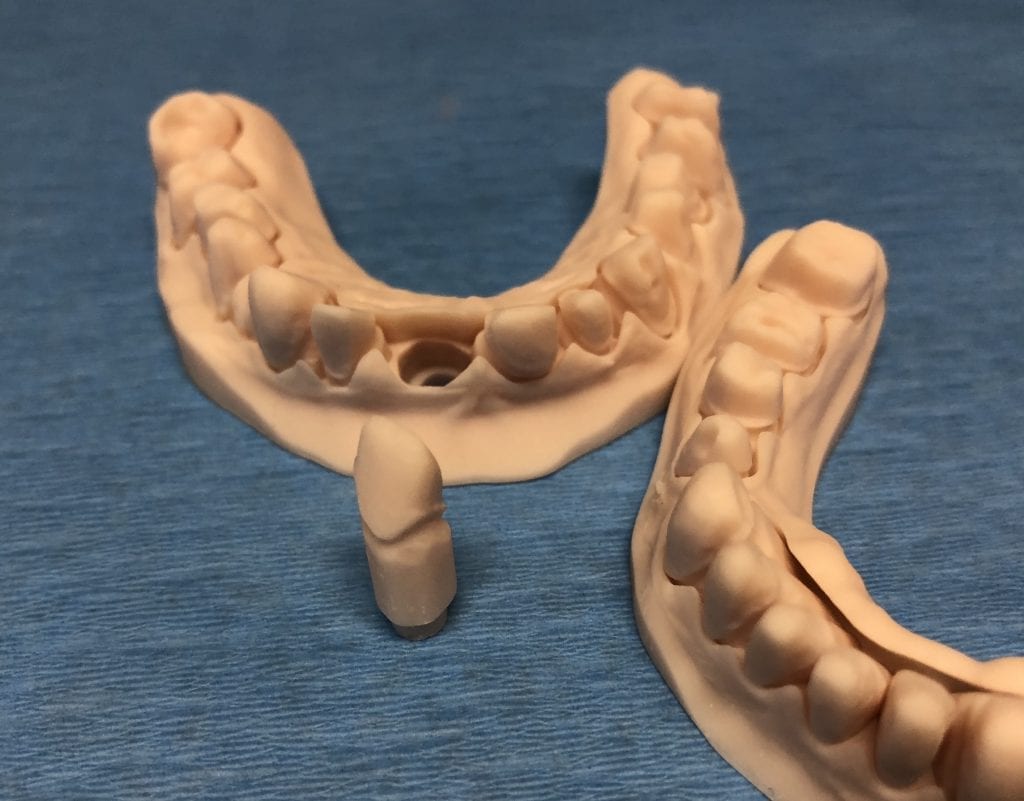

The case was designed by CADENT BESSA, and the models were printed by Burbank Dental Lab with Carbon Printers. There restorations were milled and cut back and layered by Burbank Dental Lab

IMAGES OF PRINTED MODELS